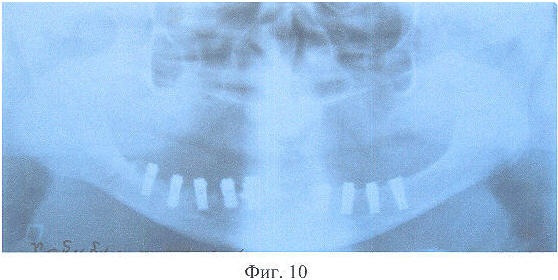

На фиг.10 – рентгенограмма больной X. после дентальной имплантации.

Больной в толщу тела нижней челюсти введено восемь дентальных имплантатов из никелида титана с пористой шейкой (Пат. Рф №2098043, М.кл А61С 8/00, 1995 г.). Через 3,5 мес. на нижнюю челюсть изготовлен несъемный зубной протез с опорой на дентальные имплантаты согласно разработанного способа, на верхнюю – полный съемный зубной протез (Пат. РФ №2270636, М.кл А61С 13/007, 2004 г.).